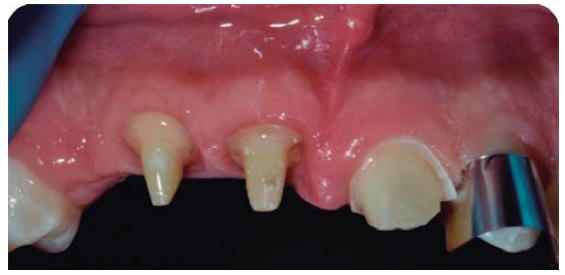

Paciente masculino de 21 años de edad, sano, presentando LDT al caer de una bicicleta; con fractura coronaria complicada de los dientes: 12, 11 y 21, con una evolución de 48 horas (Figura 1).

Debido a la evolución de dos días desde el accidente, el paciente presenta dolor e inflamación a la exploración extraoral, durante la exploración intraoral se observa la exposición pulpar de los dientes involucrados (Figura 2) e indica el tratamiento de urgencia a seguir, para disminuir el dolor e inflamación.

Paciente de sonrisa gingival que presenta fractura complicada de corona del diente 21 en el tercio medio coronal (Figura 3) y del diente 12 en el tercio cervical (Figura 4), fractura complicada de corona y raíz del diente 11 (Figura 5); gingivitis inducida por placa dentobacteriana (Figura 7), trasposición de los dientes 13 y 14, anodoncia verdadera de los dientes 15, 35 y 45, presentando los dientes temporales 55, 75 y 85.